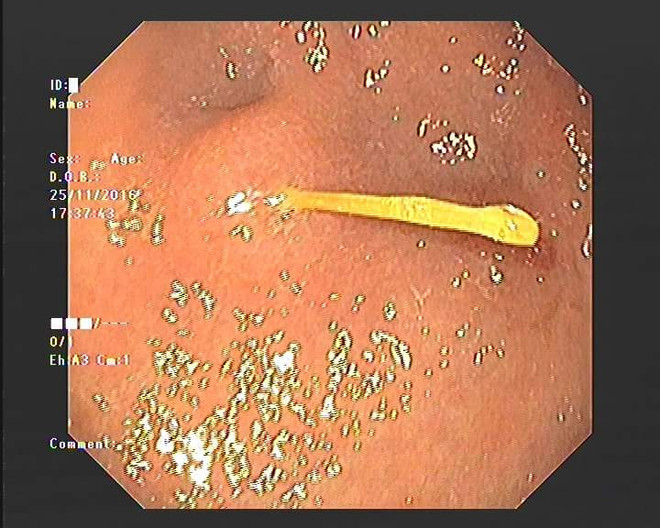

Sơ ý nuốt tăm vào bụng, một phụ nữ suýt thủng dạ dày ảnh 2Ảnh chụp chiếc tăm trong bụng của bệnh nhân. (Nguồn: Bệnh viện E)

Bệnh nhân nhập viện trong tình trạng đau vùng thượng vị dữ dội. Khi nội soi, các bác sỹ phát hiện có vật nhọn nằm ở hang vị dạ dày.

Sau khi gắp dị vật ra, các bác sỹ cho biết, đó là cây tăm tre xỉa răng.